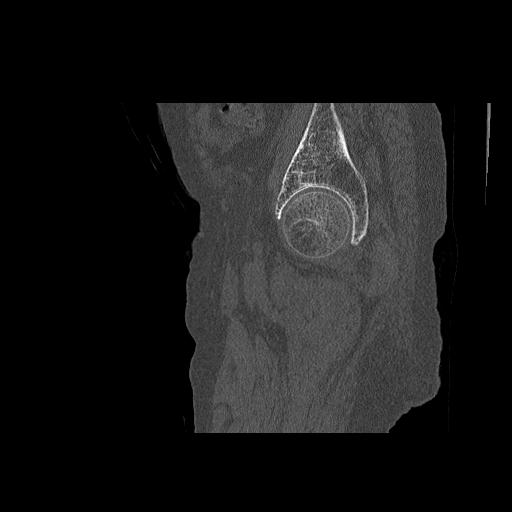

49554 3/13 膝 4R 3/16 4R 1/18 2R 78歳男性 膝蓋骨骨折